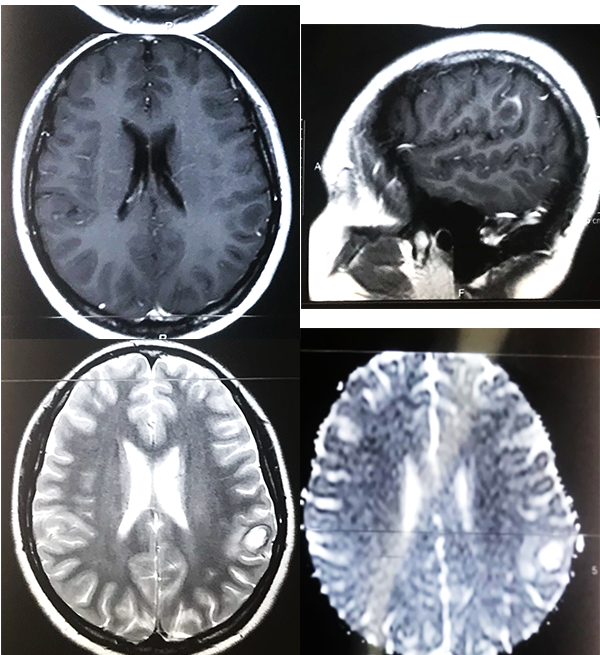

Paciente femenino de 23 años, oriunda de Bolivia, radicada desde hace 5 años en Argentina, dedicada a actividades de agricultura sin aparente nexo con cerdos, quien acude a consultorio externo por presentar cefalea intermitente de moderada intensidad, asociada a hipoestesia de mano derecha. Trae consigo una TC de cerebro simple de 30 días previos al ingreso donde se evidencia a nivel frontoparietal izquierdo lesión ocupante de espacio hipodensa con halo periférico espontáneamente densa y calcificaciones periféricas. Mide aproximadamente 22,5 mm x 16 mm y está asociado a edema de la sustancia blanca periférica, generando efecto de masa local, provocando borramiento de surcos y suturas a dicho nivel; está asociado a colapso pasivo del ventrículo lateral izquierdo (figura 1). RM con contraste visualiza imagen hipointensa en T1, hiperintensa en T2 y restricción en la difusión (figura 2).

Figura 2: RM preoperatoria. A. Corte axial T1, lesión de centro hipointenso con realce periférico. B. Corte sagital en T1 con contraste, se ubica lesión en región postcentral, imagen en anillo C. Corte axial en T2 se visualiza lesión hiperintensa con edema perilesional. D. en difusión se visualiza incremento del coeficiente de difusión aparente.